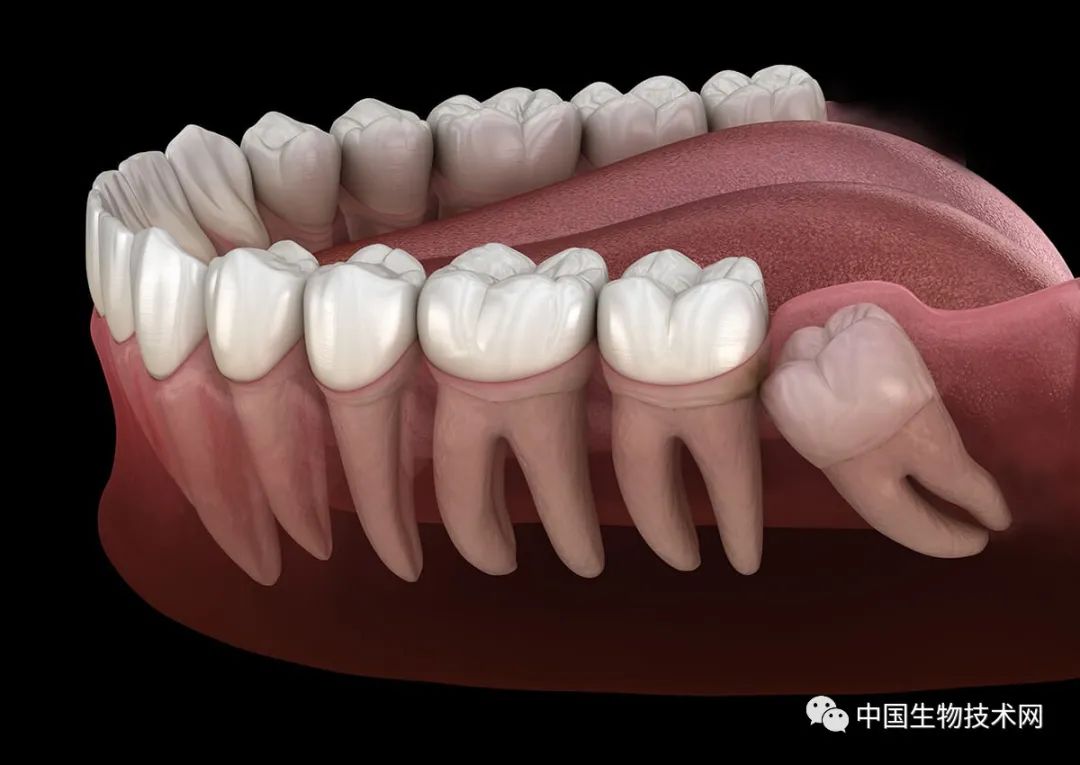

在人類近親中,只有黑猩猩像我們一樣會延長在關鍵發育期的時間。但即使是黑猩猩,也早早長齊了滿口牙。而現代智人直到青春期結束才開始萌出第三磨牙,即阻生智齒(俗稱智齒)。健康的智齒可以幫助咀嚼,但有問題的智齒可能會引起牙齦組織發炎和感染,最終導致冠周炎。所以,很多人不得不拔掉有問題的智齒。

限制牙齒萌出時間的一個重要因素是空間。如果下頜不夠大,就無法放下全套的成年牙齒,那麼也就沒必要把它們全都塞進去。

早期人類的口腔空間並不像現在這樣大,阻生智齒(俗稱智齒)是我們人類面臨的一個主要問題。但這並不能解釋為什麼它們在我們的生命中出現得這麼晚,或者為什麼後面的那些智齒似乎總在製造麻煩。

不過,有一個供牙齒生長的空位並不意味着把它放在那裏是一個好主意。牙齒不會自行咀嚼,需要大量的肌肉和骨骼支撐它們,以確保足夠的壓力可以安全磨碎食物。